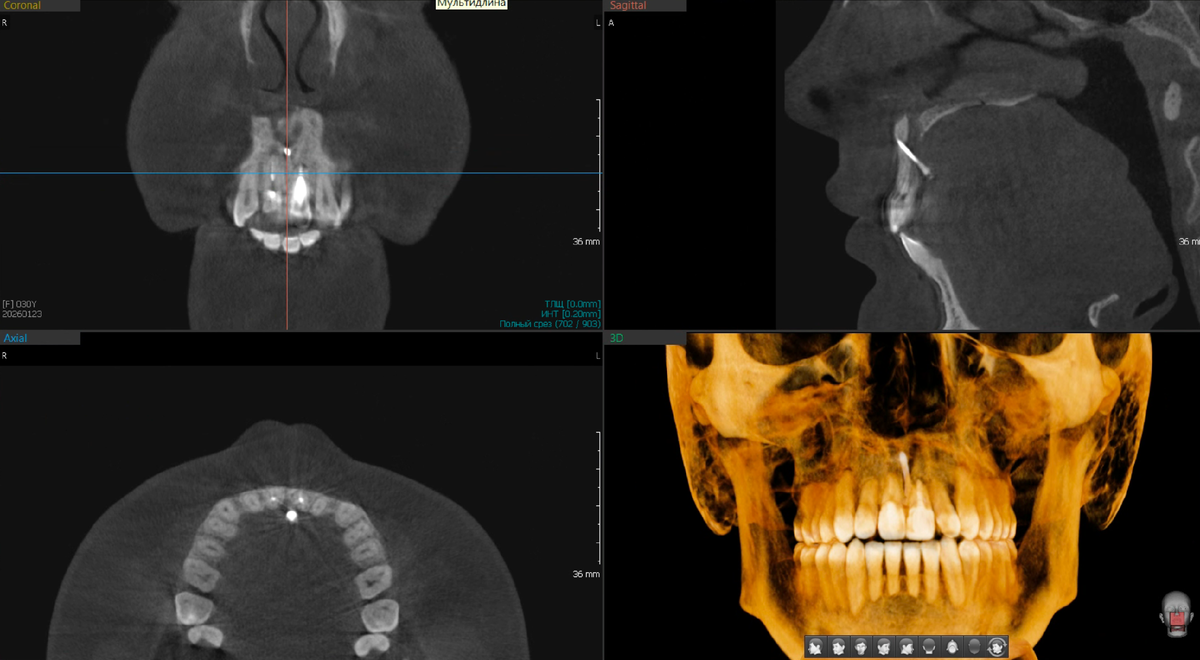

Вот что увидела ортодонт при просмотре снимка КТ:

От кортикальной пластинки кости (особенно в области резцов на нижней челюсти), от этой плотной наружной оболочки, которая удерживает зуб в лунке и обеспечивает стабильность - практически ничего не осталось. Костная ткань в критическом состоянии. Часть нижних резцов имела подвижность, корни оголены, корни резорбированы.

Это результат многолетнего процесса, в котором зубы перемещались снова и снова, кость не успевала восстанавливаться, а контроль за состоянием пародонта, судя по всему, был недостаточным. Ортодонтия - это не только про прямые зубы. Это про нагрузку на кость, про кровоснабжение, про здоровье тканей вокруг зуба. Когда этим пренебрегают, получается проблема той или иной степени тяжести.

На скрине КТ выше в области резцового канала и "винта" костный дефицит. Возможно, так и было до ортогнатической операции. Возможно - не было. КТ до нет.